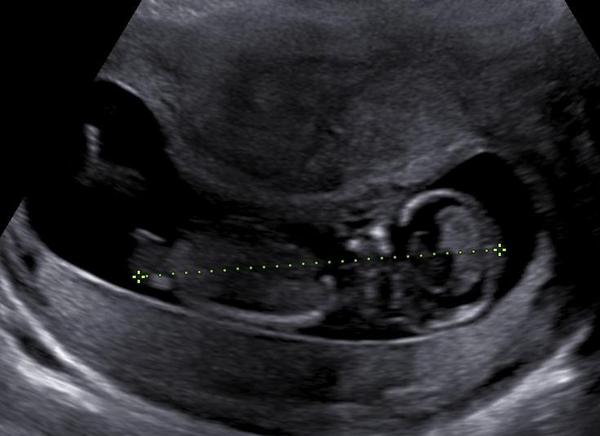

Pohlaví: Jaký je váš názor, holky?

Tak holky co myslíte😀

Holky, podle čeho to poznáte?😊🧡

@terezie90 Pohlavní hrbolek 😊